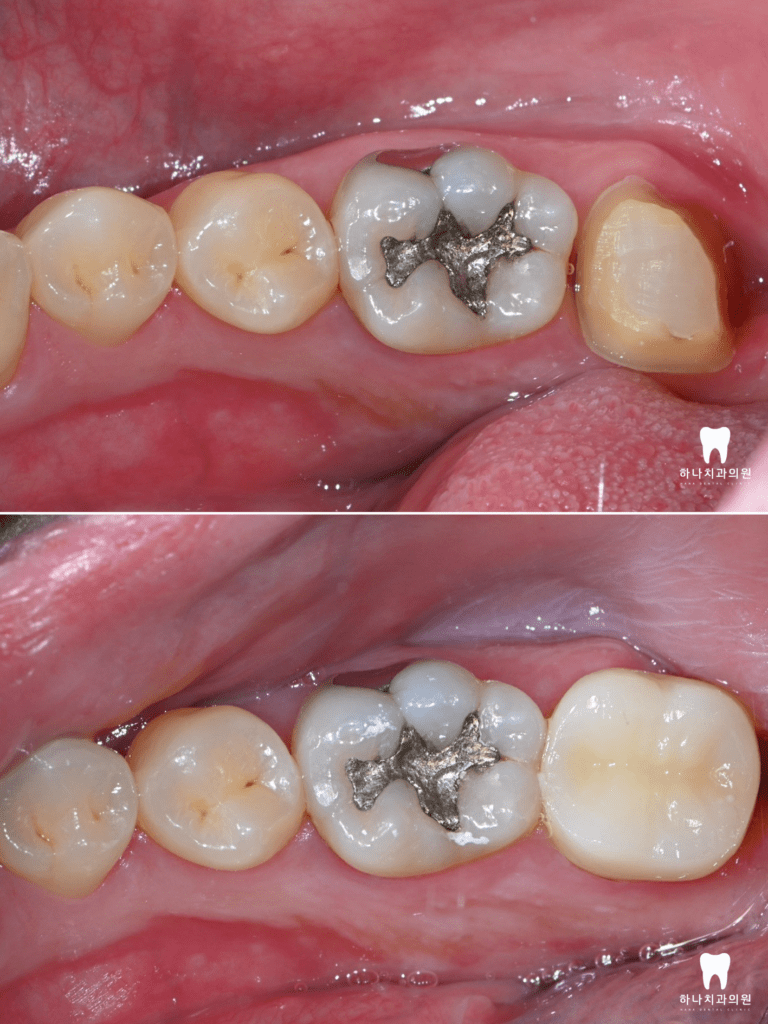

왼쪽의 경우 우식이 숨겨져 있어

잘 보이지 않았으나, 인접면 인레이를

잘 마무리하였습니다.